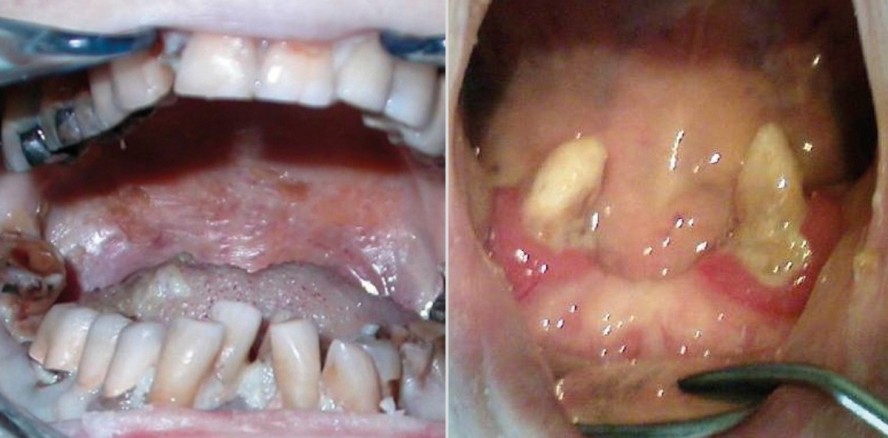

Von der Empfehlung einer Räumung zur Empfehlung, die Frontzähne mit Komposit zu erhalten.

Im Laufe einer demenziellen Entwicklung kann ein weitreichender Zahnzerfall entstehen. Erstaunlicherweise ist er praktisch schmerz- und medizinisch harmlos. Die ästhetische Einbuße bewirkt bei den Angehörigen jedoch oft dringende Behandlungswünsche. Sie sind ohne Anästhesie erfüllbar, wenn der Zahnarzt reizarm arbeitet. Die folgenden Beobachtungen entstanden im Laufe der letzten 30 Jahre im Alzheimer Kompetenzzentrum in Wetzikon (Sonnweid) und in der Praxis des Autors.

Die Bewohner befinden sich im zweiten Stadium in der Pflegeabteilung und werden Tag und Nacht betreut. Sie benötigen Hilfe beim Ankleiden, Essen, Auffinden ihrer Zimmer usw., und oft befällt sie eine motorische Unruhe (Wandertrieb). Sie sprechen unverständlich, aber Angehörige können den Sinn erahnen. Unangenehme Reize wehren sie energisch ab. Mit dem Erstarren der Muskeln und Gelenke hören die Kaubewegungen auf und flüssige Nahrung wird notwendig. Die festen Lippen, Wangen und die Zunge verunmöglichen jede wirksame Mundhygiene und erzeugen einen übermäßigen, meistens nach oral gerichteten Druck gegen die Zähne. Wegen des Ausbleibens der Kautätigkeit entstehen Elongationen und die Okklusion wird dysfunktional (Abb. 1). Die Frontzähne dienen aber noch zum Nagen (an der Bettwäsche), zum Fletschen (bei Angst vor einem Unbekannten) und zum Beißen (zur Abwehr einer unerwünschten Person). Typisch sind erste Wurzelreste bei den Molaren und große, labiale Frontkaries.

Um sicher zu sein, dass keine versteckten Granulome oder andere pathogene Veränderungen in den Kieferknochen vorlagen, wurden 2007 mit Bewilligung der Ethikkommission in Bern die Zähne von zehn verstorbenen Alzheimerpatienten ge-röntgt. Es fanden sich bei über 100 kariösen Zähnen und Wurzelresten nur wenige apikale Aufhellungen von lediglich einem Millimeter Größe, die meisten Wurzelreste waren deutlich verkürzt und die Pulpen weitgehend obliteriert (Abb. 4). Bei einem Molar mit schwerer Parodontitis war nur noch die palatinale Wurzel im Knochen verankert. Die anderen beiden Wurzeln befanden sich außerhalb des Zahnfleisches (Abb. 5).

2017 wurden die ersten Kompositfüllungen an zwei Frontzähnen bei einer Patientin im zweiten Stadium gemacht.

Indikation: Erhalt der Frontzähne ohne Narkose im Wissen um die lebenslang große ästhetische Bedeutung und nun basale Funktion dieser Zähne für die Patientin (Abb. 7).